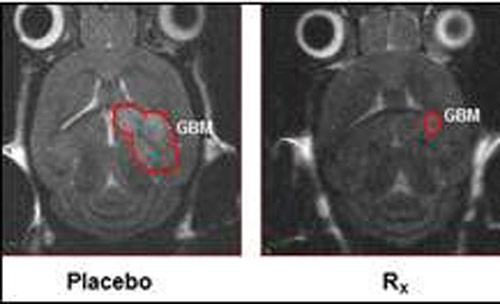

Hình ảnh cho thấy khối u não chuột nhỏ lại (bên phải) do được trị liệu bằng SHP2 Ảnh: MEDICAL XPRESS

Trong công trình được công bố trên tạp chí Nature Communications, nhóm nghiên cứu đã phát hiện protein khác được gọi là SHP2 có thể “bật tắt” hoạt động của Ras. Cùng với đồng nghiệp Mỹ tại ĐH Indiana, họ đã thử nghiệm khả năng ức chế của SHP2 trên chuột bị ung thư não và nhận thấy khối u bị thu nhỏ đến 80%.